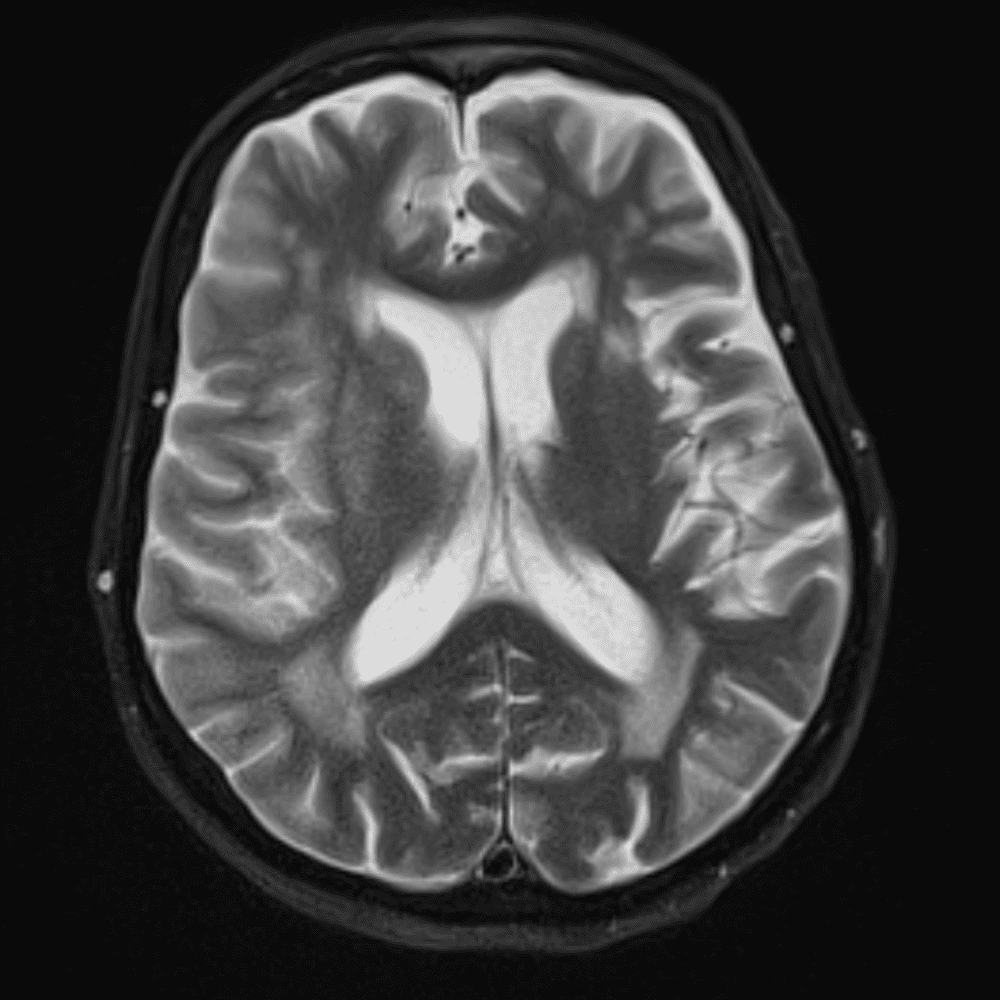

๋‹น์ง ์‹œ ํ”ํžˆ ๋ณผ ์ˆ˜ ์žˆ๋Š” ์‚ฌ๋ก€์˜ ์ „ํ˜•์ ์ธ ์˜ˆ๋ฅผ ํฌํ•จํ•ฉ๋‹ˆ๋‹ค.

39 ์‚ฌ๋ก€

์—ฐ์Šต

๋ฏธ๋ฌ˜ํ•˜๊ฑฐ๋‚˜ ์–ด๋ ค์šด ์‚ฌ๋ก€์™€ ์ผ๋ถ€ ์ •์ƒ ์‚ฌ๋ก€๋ฅผ ํฌํ•จํ•˜์—ฌ ๋‹น์ง์„ ์‹œ๋ฎฌ๋ ˆ์ด์…˜ํ•ฉ๋‹ˆ๋‹ค.

50 ์‚ฌ๋ก€